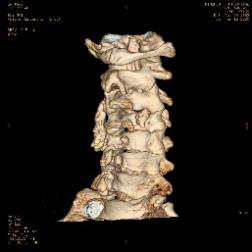

术前脊髓造影后颈椎CT。

颈椎间盘突出明显。